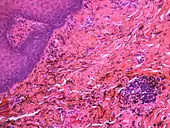

Granular deposits of silver sulfide along elastic fibers of the connective tissue of the oral mucosa. Low chronic inflammatory changes in the form of a lymphocytic aggregate (bottom right)

Silver sulfide deposits are found in proximity to small vessels in the oral mucosa

Silver sulfide deposits in the surrounding area of skeletal muscle fibers of the oral mucosa

If necessary, the diagnosis can be confirmed histologically by excisional biopsy, which excludes nevi and melanomas.[3]:138 If a biopsy is taken, the histopathologic appearance is:[1]

• Pigmented fragments of metal within connective tissue

• Staining of reticulin fibers with silver salts

• A scattered arrangement of large, dark, solid fragments or a fine, black or dark brown granules

• Large particles may be surrounded by chronically inflamed fibrous tissue

• Smaller particles surrounded by more significant inflammation, which may be granulomatous or a mixture of lymphocytes and plasma cells